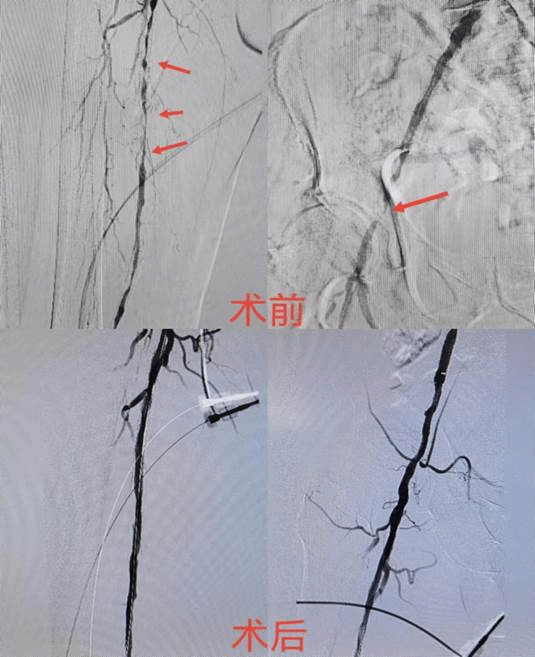

介入血管外科李威教授详细了解患者病情后,为其紧急相关完善检查,发现患者下肢动脉闭塞情况十分严重,如不及时治疗很可能因为血液供应不足,造成组织细胞萎缩或坏死导致截肢风险,决定马上为其进行手术治疗。

根据病人病情,李威教授为患者行血管腔内介入治疗。术后患者疼痛症状即刻缓解,效果显著。李威教授介绍,经过腔内介入治疗,患者最大程度的保留了肢体功能,避免了截肢的后果,同时为病人解除了痛苦,极大地提高了患者的生活质量,使患者最大程度的恢复健康,保障了他们的正常生活。